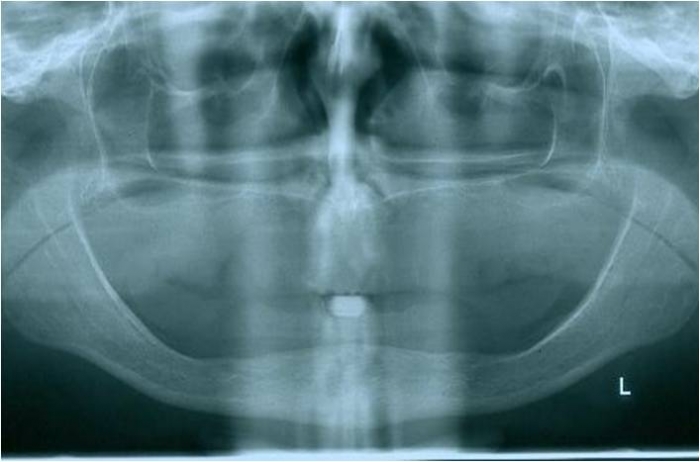

Raio x inicial - Clínica Cliniface

Raio x inicial